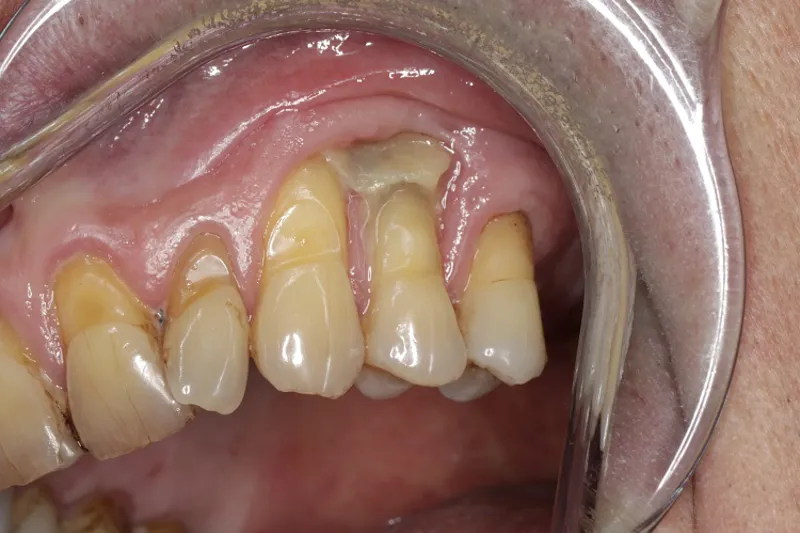

En 66-årig mand blev henvist til Tand-, Mund- og Kæbekirurgisk Afdeling, Aarhus Universitetshospital, grundet blotlagt knogle i venstre side af overkæben. Patienten havde aldrig modtaget antiresorptiv medicin eller strålebehandling, ej heller kendt med knoglesygdom.

Tænderne +3, 4, 5 var intakte, men med patologiske pocher og pus ved sondering. Klinisk og røntgenologisk blev der registreret sekvesterdannelse. Der blev foretaget fjernelse af +3, 4, 5 med samtidig sekvestrektomi, oprensning og primær aflukning med platelet-rich fibrin og bløddelslap under antibiotikadække. Den histologiske undersøgelse viste forandringerne forenelige med knoglesekvester. Efterfølgende ukompliceret heling.